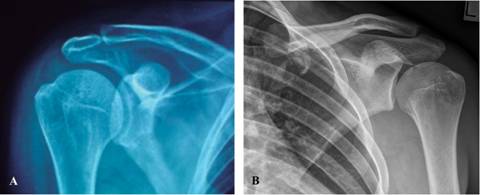

Hill Sachs Lesion With Bony Bankart Lesion Radiology Case

Inestabilidad Glenohumeral Anterior Bankart Oseo Y Hill Sach Con